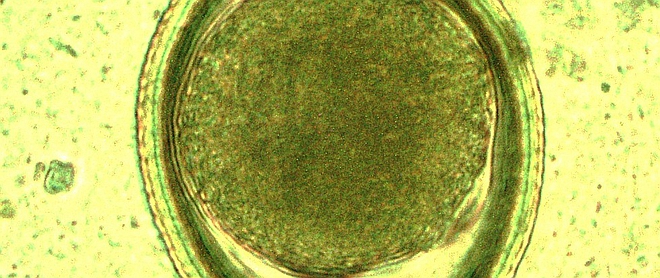

Pobranie kału człowieka lub zwierzęcia do badania parazytologicznego jest proste i nieinwazyjne. Badanie to jest skutecznym instrumentem diagnostycznym pozwalającym na identyfikację zagrożenia inwazją pasożytniczą. Wykonywane okresowo parazytologiczne badanie kału zwierząt domowych daje właścicielom informację o potrzebie leczenia zwierzęcia, zapobiegając niepotrzebnemu podawaniu środków przeciwrobaczych i umożliwiając precyzyjne dobranie najskuteczniejszego leku. Daje ono także informację o potencjalnym ryzyku zarażenia się chorobą odzwierzęcą osób kontaktujących się ze zwierzęciem.